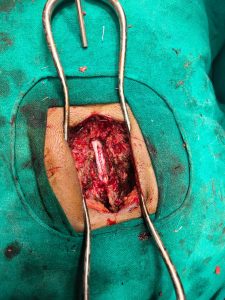

मधेश प्रदेशमा पहिलाे पटक जानकी एकेडेमीक हस्पिटलमा डा.प्रधुम्न कुमार यादव र वहाँ काे टिम ले Neuro Surgical of Spinal (D6 Spine Tumer excision ) केश सफलतापुर्ण अप्रेसन गरिएकाे छ । अहिले सम्म यस्तो जटिल (D6 Spine Tumer) को अप्रेसन धनुषा जिल्ला को जनकपुर र विरगंजमा मा पनि भएकाे छैन ।